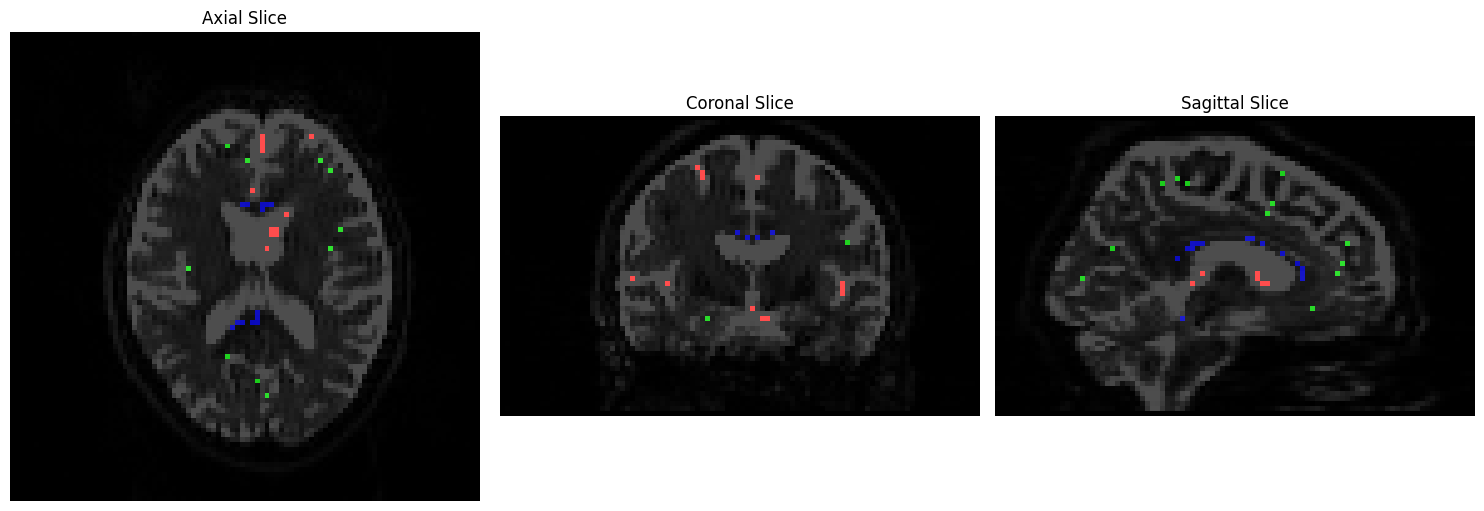

We will visualize the voxels used to construct a basis function for each tissue type using Matplotlib. CSF voxels should be colored red, gray matter voxels green, and white matter voxels blue:

rgb_overlay[..., 0] = data2[..., 0] # Red for CSF

rgb_overlay[..., 1] = data2[..., 1] # Green for GM

rgb_overlay[..., 2] = data2[..., 2] # Blue for WM